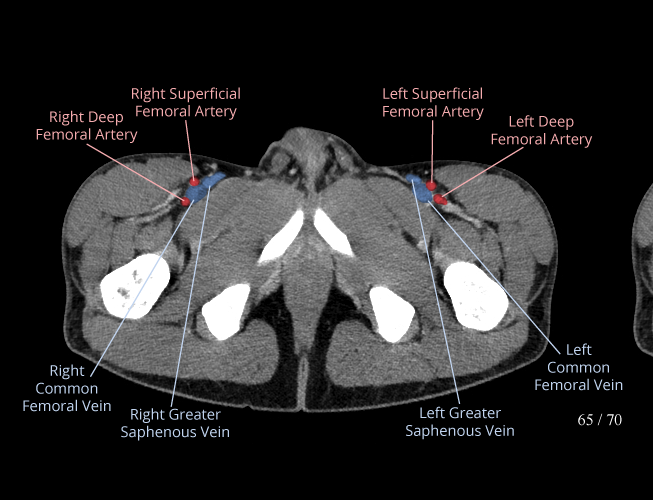

Body

Covers abdominal CT anatomy.